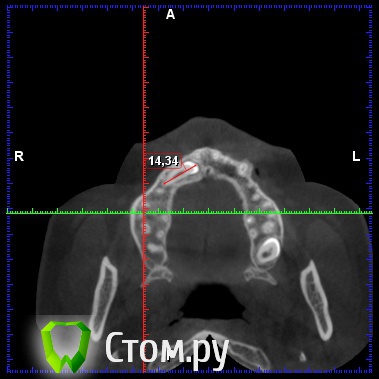

diesel87 Опубликовано 19 декабря, 2013 Поделиться Опубликовано 19 декабря, 2013 Обратилась пациентка, ретенированный 13, располагается горизонтально, брекет систему ставить не хочет, просит удалить этот клык и поставить на его место имплантат, меня интересует вот что, клык то я удалю, что с последующей имплантацией и когда ее провести, просто по кт клык залегает перпендикулярно ось имплантата, прилагаю срезы кт Ссылка на комментарий

diesel87 Опубликовано 19 декабря, 2013 Автор Поделиться Опубликовано 19 декабря, 2013 Меня интересует, как быть с отсутствием кости после удаления, размером с клык, если сразу то есть около 7 мм по вертикали, а потом провал в 4,5 мм и снова кость Ссылка на комментарий

diesel87 Опубликовано 5 января, 2014 Автор Поделиться Опубликовано 5 января, 2014 Планирую удаление, сразу графт и походу может быть винт,хотел по размеру винта проконсультироваться, по КТ расстояние от 14 до 12 зубов 7,2 мм а по вестибулярно-щечному 5,42, с небной стороны не большой провал из-за небного положения клыка, и по длине интересует 12 или 14 ми, планирую 3,8 на 12. Ссылка на комментарий